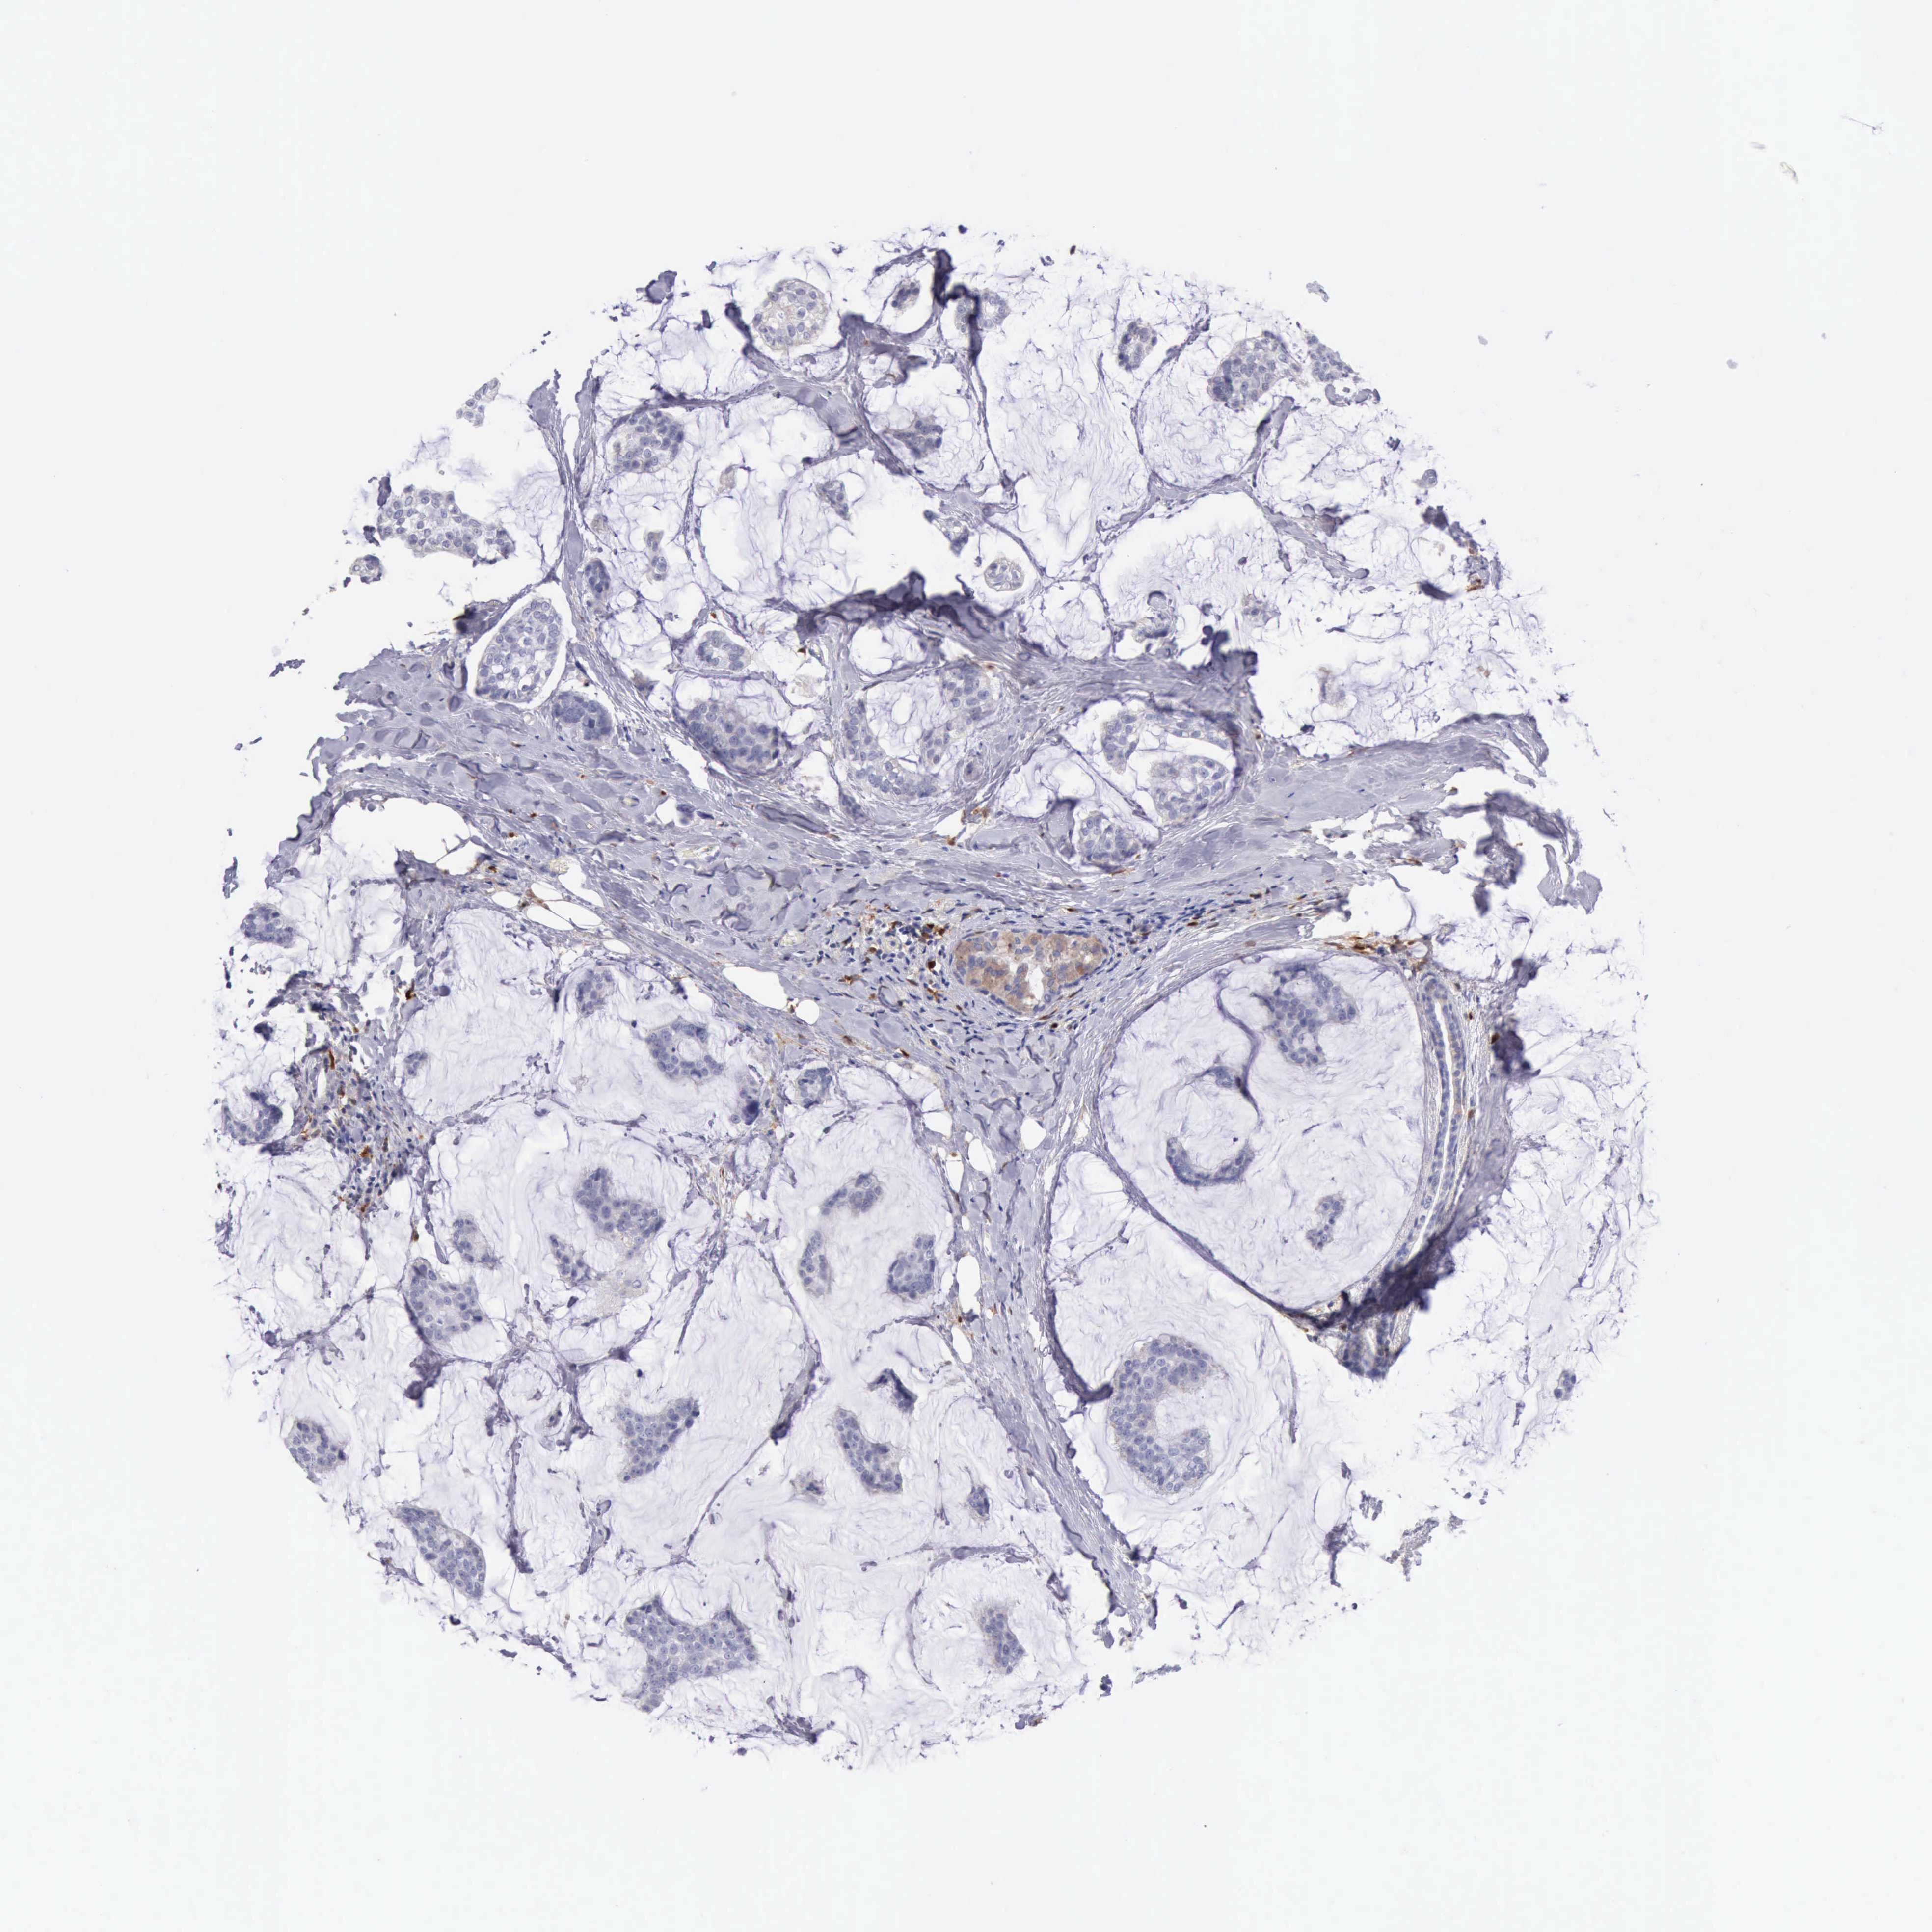

CANCER BREAST CANCER Show tissue menu

BRCA TCGA BRCA VALIDATION PROTEIN EXPRESSION